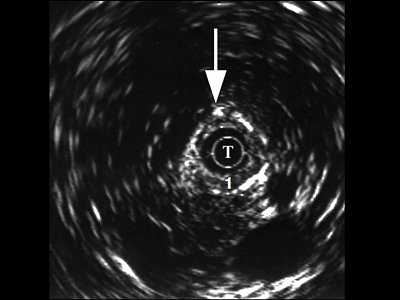

При интрауретральной ультрасонографии в неизмененных отделах мужской уретры по мере проведения датчика мы определяли головку полового члена, губчатое тело, кавернозные тела с окружающими их оболочками, сосуды. В более широком луковичном отделе регистрировались спонгиозная ткань с более тонкой стенкой и прикрепляющимися к ней мышцами (рис. 2).

Рис. 2. Эхограмма нормального луковичного отдела уретры, Т - трансдуктор.